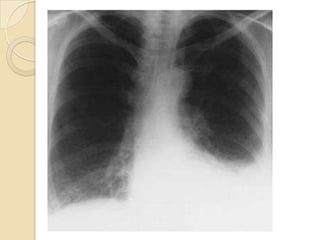

RADIOGRAFIA DE TORAX

 No se puede detectar la etiología del

derrame

 Hallazgos: borramiento del ángulo

costofrénico u opacificación de la base

del hemitórax.

 El líquido forma una concavidad

superior denominada Menisco Pleural.

   Desplazamiento del mediastino hacia el

lado contrario al derrame.

   En las radiografías laterales pueden

identificarse cantidades de líquido a partir

de 25-50 ml, y en las PA a partir de unos

200-300 ml